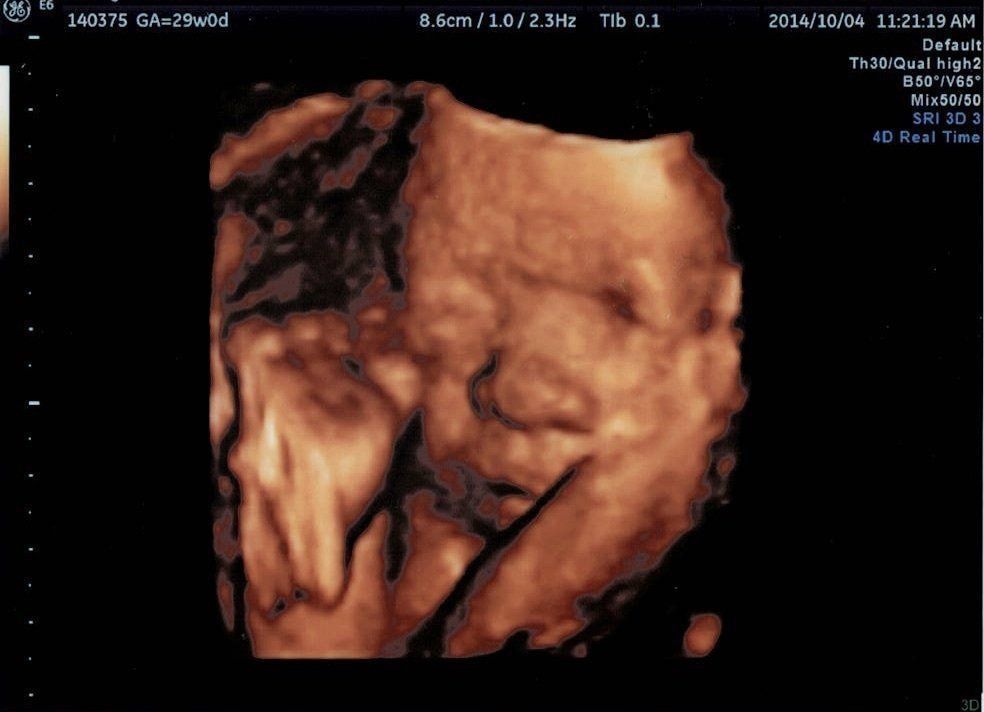

妊娠29週目エコー写真

二度目の4Dエコーでした。また顔を隠していたのですが、どうにか動いて顔を見せてくれました。大きめのお鼻が主人にそっくり!あまりにも似ていて夫婦でしばらく笑い転げました。生まれる前からお父さん似と判明。主人は「自分の子どもだって納得できた」などと失礼なことを言っていました。でも、主人が我が子を受け入れる心の準備になったのは確かです。